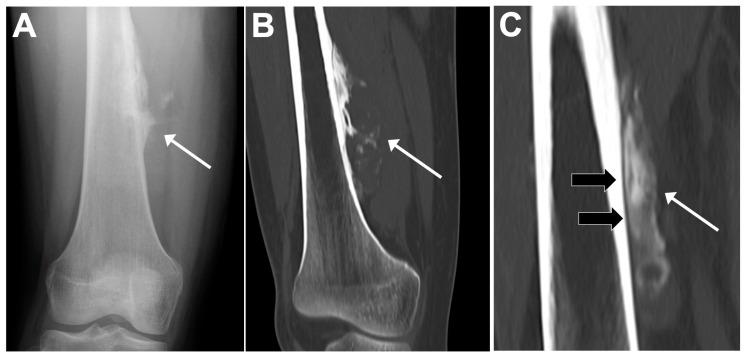

Osteosarcomas are rare malignancies (<1% of all cancers) that produce an osteoid matrix. Osteosarcomas are the second most frequent type of primary bone tumor after multiple myeloma and the most prevalent primary bone tumor in children. The spectrum of imaging findings of these malignancies varies significantly, reflecting different histological subtypes. For instance, conventional osteosarcoma typically presents with a mixed radiological pattern (lytic and bone mineralization) or with a completely eburneous one; aggressive periosteal reactions such as sunburst, Codman triangle, and soft-tissue components are frequently displayed. On the other hand, telangiectatic osteosarcoma usually presents as a purely lytic lesion with multiple fluid-fluid levels on MRI fluid-sensitive sequences. Other typical and atypical radiological patterns of presentation in other subtypes of osteosarcomas are described in this review. In addition to the characteristics associated with osteosarcoma subtyping, this review article also focuses on imaging features that have been associated with patient outcomes, namely response to chemotherapy and event-free and overall survivals. This includes simple semantic radiological features (such as tumor dimensions, anatomical location with difficulty of radical surgery, occurrence of pathological fractures, and presence of distant metastases), but also quantitative imaging parameters from diffusion-weighted imaging, dynamic contrast-enhanced MRI, and 18F-FDG positron emission tomography and radiomics approaches. Other particular features are described in the text. Overall, this comprehensive literature review aims to be a practical tool for oncologists, pathologists, surgeons, and radiologists involved in these patients' care.

骨肉瘤是一种罕见的恶性肿瘤(占所有癌症的比例不到1%),可产生类骨质基质。骨肉瘤是继多发性骨髓瘤之后第二常见的原发性骨肿瘤类型,也是儿童中最常见的原发性骨肿瘤。这些恶性肿瘤的影像学表现谱差异很大,反映了不同的组织学亚型。例如,传统骨肉瘤通常表现为混合性放射学模式(溶骨性和骨矿化)或完全骨化模式;常显示侵袭性骨膜反应,如日光放射状、科德曼三角和软组织成分。另一方面,毛细血管扩张性骨肉瘤通常表现为纯溶骨性病变,在MRI液体敏感序列上有多个液-液平面。本文综述了骨肉瘤其他亚型的其他典型和非典型放射学表现模式。除了与骨肉瘤亚型相关的特征外,本文还重点关注与患者预后相关的影像学特征,即对化疗的反应、无事件生存期和总生存期。这包括简单的语义放射学特征(如肿瘤大小、根治性手术困难的解剖位置、病理性骨折的发生以及远处转移的存在),也包括扩散加权成像、动态对比增强MRI、18F-FDG正电子发射断层扫描和放射组学方法的定量成像参数。文中还描述了其他特殊特征。总体而言,这篇全面的文献综述旨在成为参与这些患者护理的肿瘤学家、病理学家、外科医生和放射科医生的实用工具。